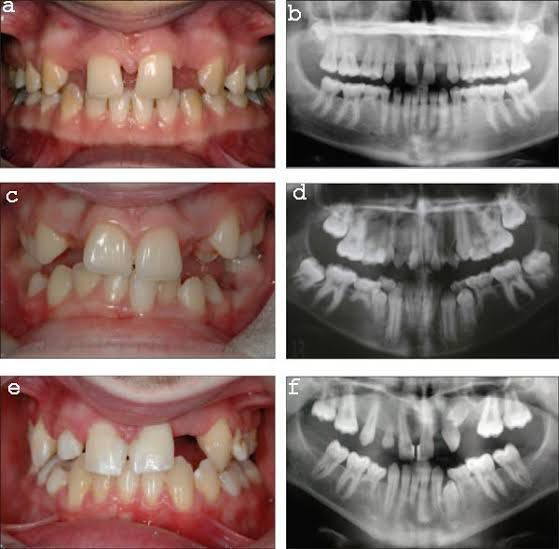

Treatment of hypodontia

Hypodontia treatments may include: Braces or other types of orthodontics. Partial dentures. Dental bridges. Dental implants. Children with hypodontia typically wear partial dentures until they’re old enough for other treatments.